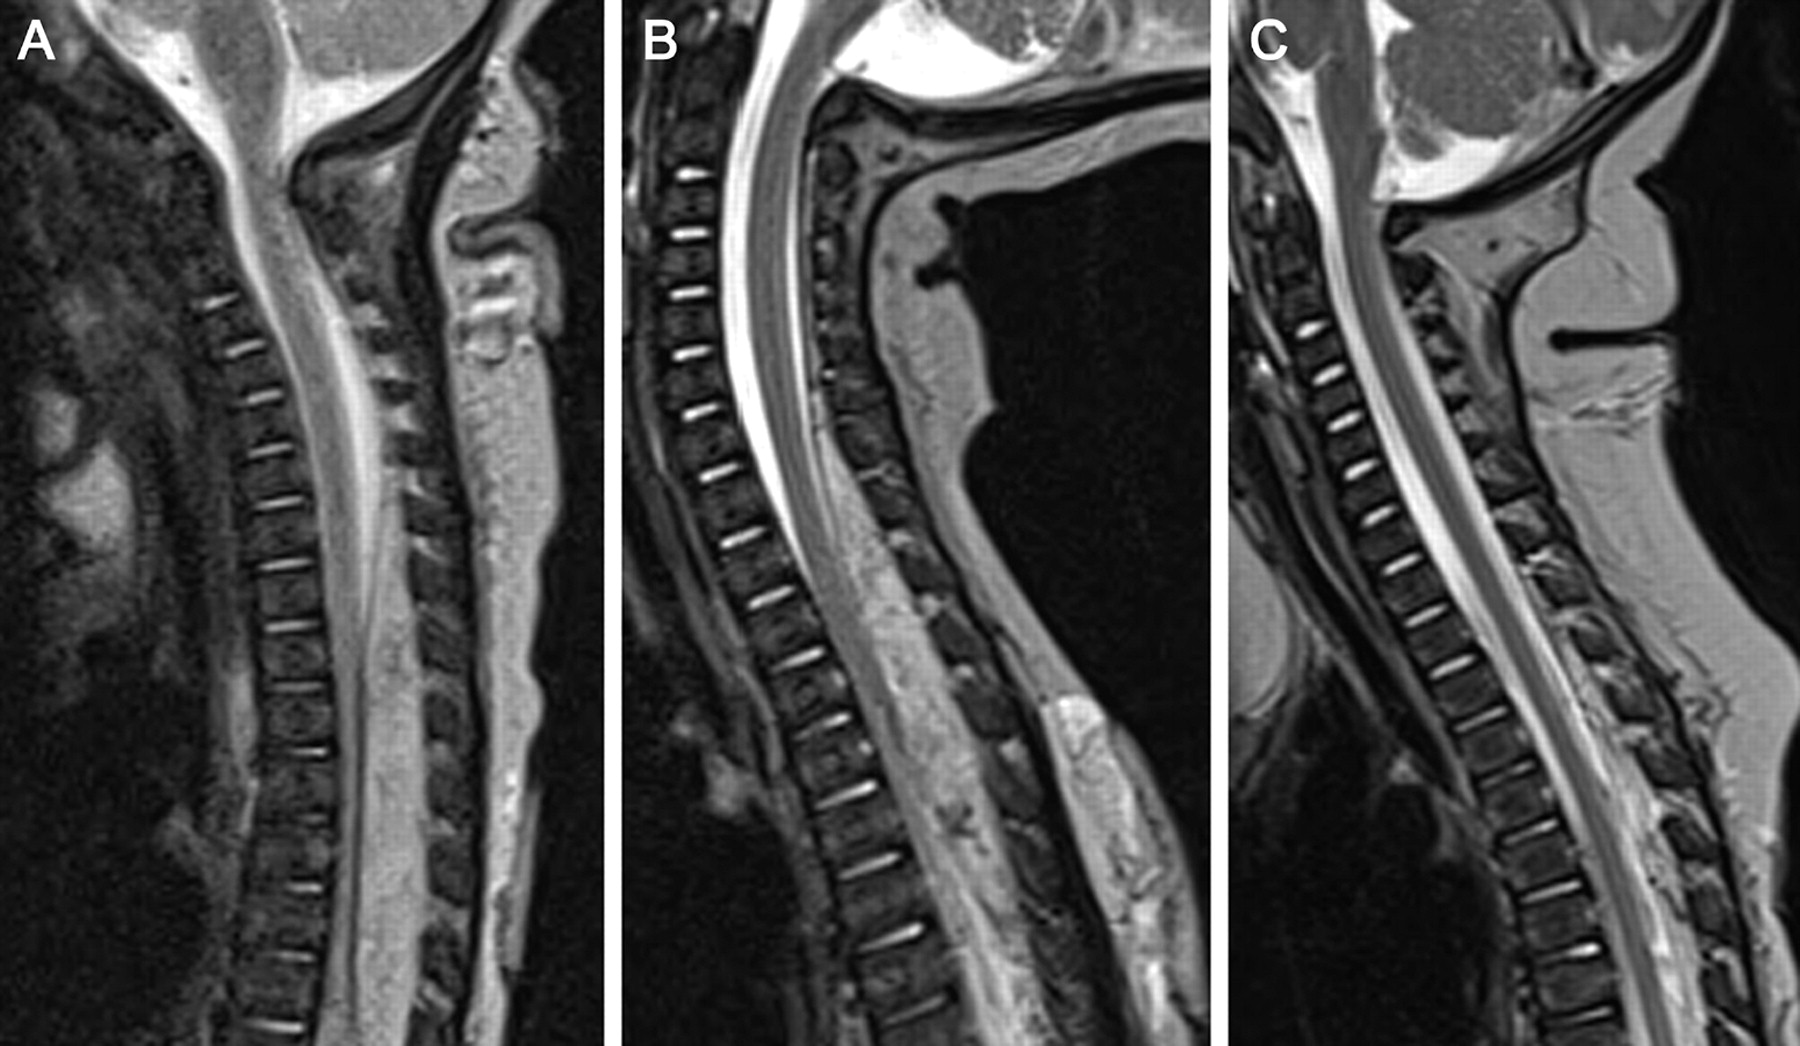

小儿脊柱内的和广泛的皮肤伤害

优秀的应对普萘洛尔